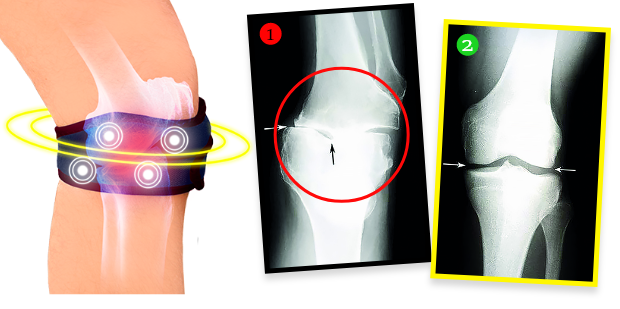

Pani Helena zrobiła po kuracji badanie RTG i okazało się, że zmiany zwyrodnieniowe w kolanie całkowicie się cofnęły! Lekarz osłupiał – nie wiedział, co powiedzieć. A fakty są takie, że dzięki biomagnetycznej opasce stan kolana pani Heleny nie tylko przestał się pogarszać. Tkanka chrzęstna i delikatne struktury w obrębie stawu zregenerowały się, a kolano wróciło do całkowitej sprawności sprzed lat. Opaska emituje bowiem naturalne i bezpieczne pole biomagnetyczne, które przenika w najgłębsze tkanki stawu, odżywiając i regenerując chrząstkę, przywracając jej elastyczność i sprężystość, a także stymuluje produkcję mazi stawowej, która amortyzuje i chroni przed bolesnym tarciem podczas poruszania się. Jest to terapia w pełni bezinwazyjna i bezpieczna.

Jeszcze 1,5 miesiąca temu miałem zniszczone, trzeszczące stawy, przez co ledwo chodziłem. Każdy większy wysiłek fizyczny sprawiał, że stawy eksplodowały bólem. Dzięki tej opasce czuję, że moje stawy są sprawne jak u nastolatka! Potwierdzają to wyniki kontrolnych badań RTG, USG i rezonansu magnetycznego. Kiedy je zobaczyłem, popłakałem się ze szczęścia. Ale kto by nie płakał? Moje kolana są jak nowe!”